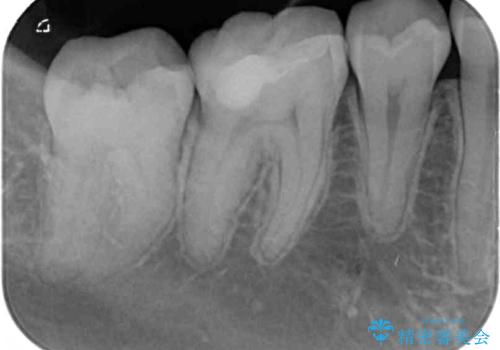

- 矯正治療後に目立つ銀歯を白くしたいとのことで来院された患者様です。

右下の銀の詰め物は、外してむし歯を除去した後、セラミックインレーにて修復することとしました。

左上の銀歯は、銀歯の下に金属の土台が入っているため、その土台を除去し、ファイバーコアにやり替えて、オールセラミッククラウンにて補綴することとしました。